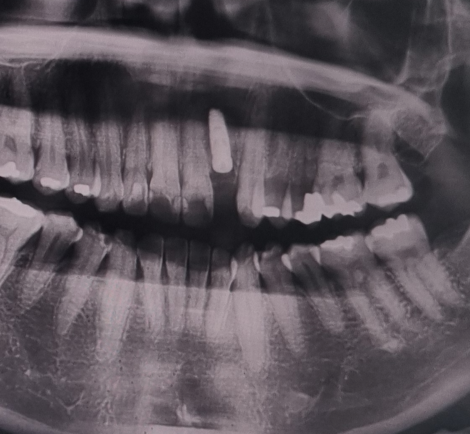

항암치료 종료 5개월 차인 저는 (항암 부작용 등으로 인해) 약해진 치아가 부러져 임플란트 치료를 시작했습니다. 첫 단계인 치아 발치와 식립을 하고, 항생제를 계속 복용 중인 상황입니다. 수술 후 언제까지 이렇게 아플지, 뭘 먹어야 하는지 계속 검색을 했었기 때문에 저처럼 이런 정보를 찾고 계시는 분들을 위해 제 경험과 주의사항 등을 오늘 포스팅에서 정리해보려고 합니다.

시술이라고도 하고, 광고도 많이 나오고 많은 사람들이 하니까 그냥 사랑니를 뽑는 수준이겠거니 했는데, 생각보다 너무 힘들고 아팠습니다. 저는 부위가 앞니였고, 뿌리밖에 남지 않은 상태였기 때문에 발치 과정이 정말 힘들었고, 수술 시작부터 원장님이 발치가 힘들 거라고 경고를 하셨어요. 당연히 마취 덕분에 발치 부위는 아프지 않았지만 뿌리밖에 안 남은 치아를 기계로 갈아내고 뽑는 시도를 하는 과정에서 주변 부위에 가해지는 압력 때문에 짧게 짧게 통증이 있었습니다.